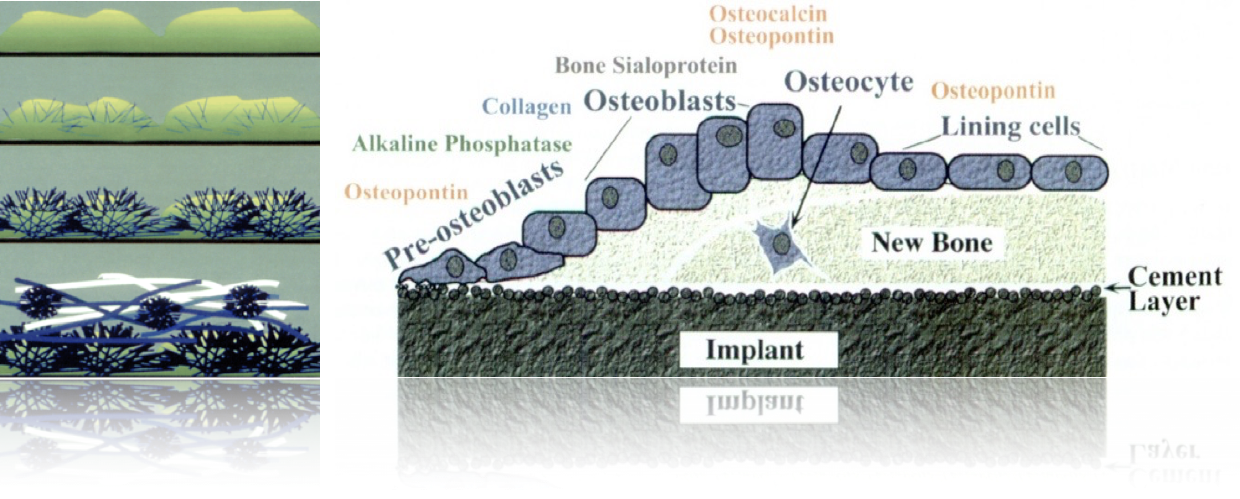

Esta ausência de micromovimentos é fundamental para obtenção dos fenômenos subsequentes, tais como: a substituição do coágulo por uma matriz óssea, a migração dos vasos para o interior da área de cicatrização, e a chegada de células mesenquimais diferenciadas. Essas células serão estimuladas com os indutores adequados que estão atuando nessas áreas (fatores de crescimento e diferenciação) e, induzam a transformação em células pré-osteoblásticas, posteriormente osteoblásticas, as quais atuarão simultaneamente aos osteoclastos na reabsorção e neoformação óssea buscando a estabilidade secundária biológica, conforme mostrado no esquema da figura 1.

Figura 01: Esquema das diversas fases da osseointegração, desde o coágulo até o osso maturado.